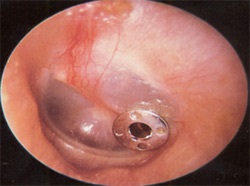

Fülfertőzések és halláscsökkenés

Gyermekek szájpadhasadék esnek egy magasabb kockázati csoportba betegségek fülgyulladás, mivel ezek hajlamosak a folyadék felhalmozódása a középfülben. Ha ez a feltétel nem kezelik, fülgyulladás kiválthatja halláscsökkenés. Ennek megakadályozására a gyermekek szájpadhasadék létre külön csövet a dobhártya, hogy a folyadék elvezetés, valamint annak szükségességét, hogy tárgyalást tart minőségi ellenőrzés évente egyszer.